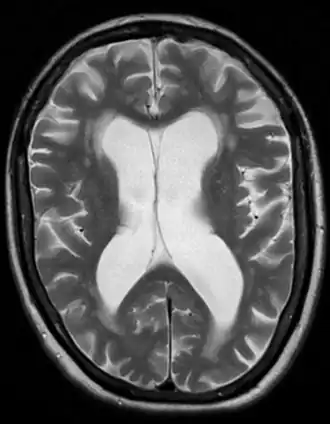

Brain atrophy from vascular dementia

Gross examination of the brain may reveal noticeable lesions and damage to blood vessels.[2][6] Accumulation of various substances such as lipid deposits and clotted blood appear on microscopic views. The white matter is substantially affected, with noticeable atrophy (tissue loss), in addition to calcification of the arteries.[2][6][17] Microinfarcts may also be present in the gray matter (cerebral cortex), sometimes in large numbers.[2]